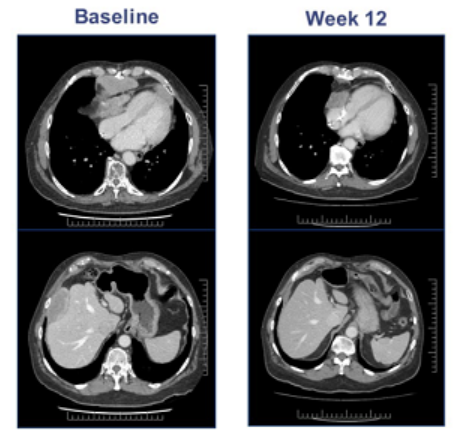

其中一位67岁的男性晚期滑膜肉瘤患者,MAGE-A4高表达(100%),接受9.95*10^9ADP-A2M4 T细胞治疗12周后,最大的肿瘤病灶(155mm)缩小了45%,随着进一步的治疗,肿瘤缩小了71%。